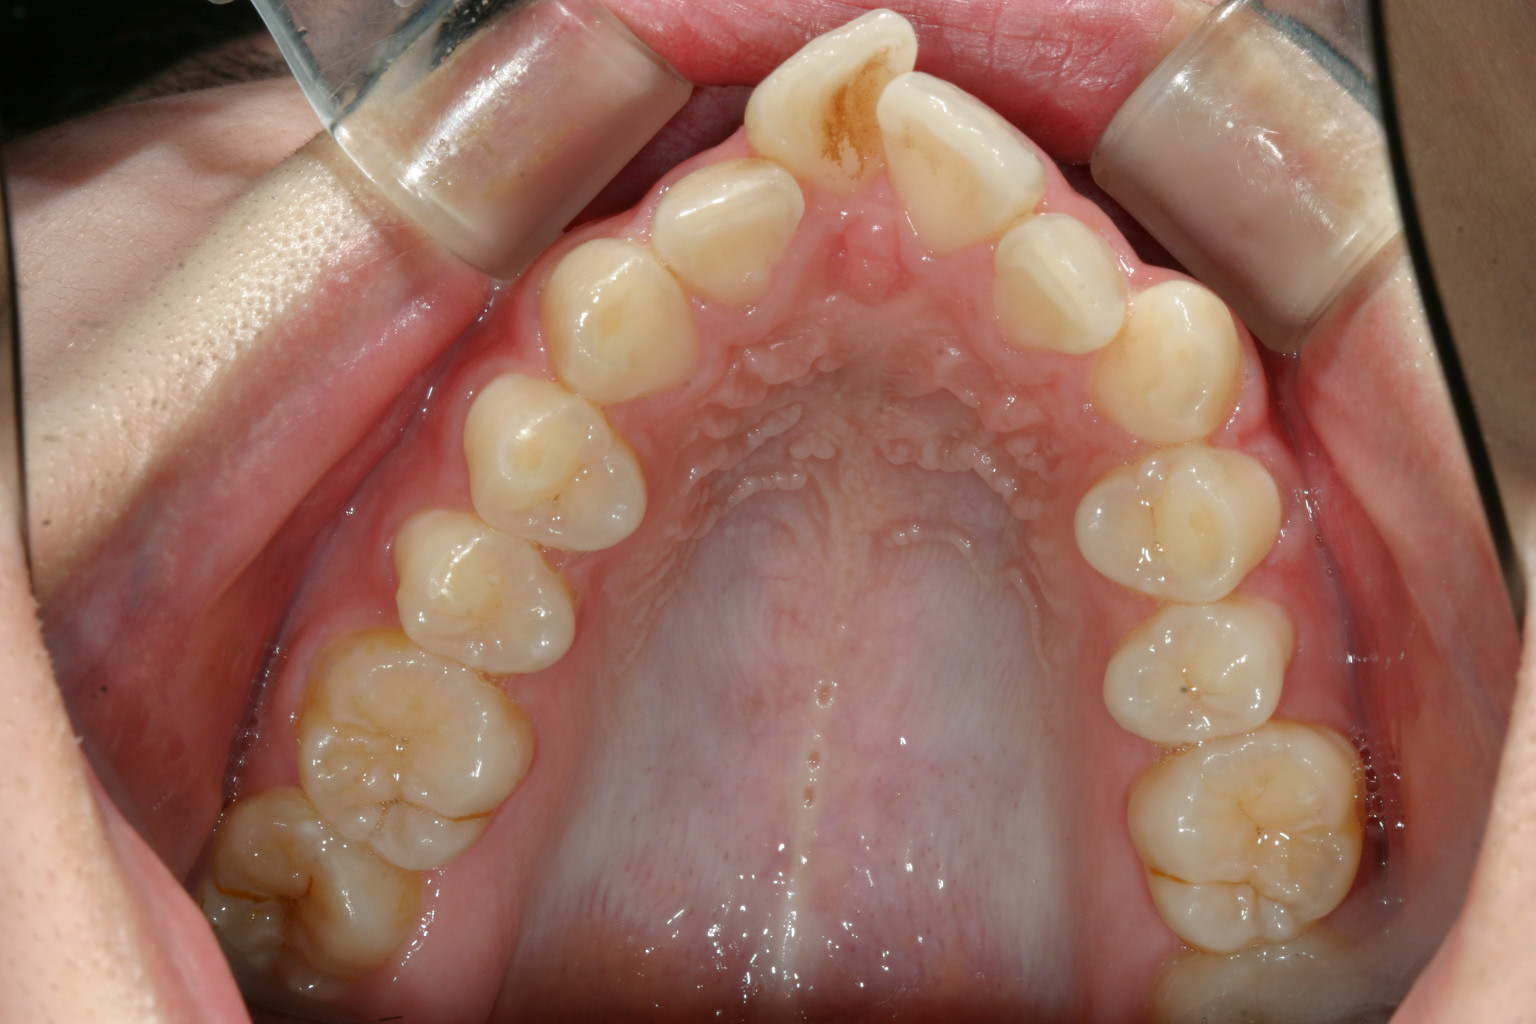

歯列がV字型になってます。

上の歯列がV字型ですから下顎もV字型です。

この様に上下の歯列がV字になることにより口ボゴが生じてます。犬歯と犬歯の間が狭い為に前歯4本が並ぶことが出来ない為仕方なくV字の歯列になった珍しい症例です。